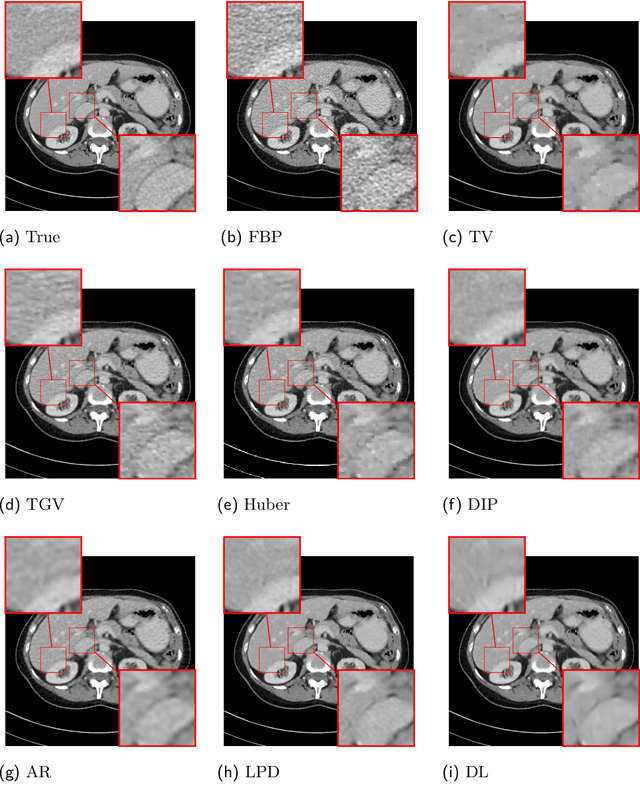

Abstract:This work presents an approach for image reconstruction in clinical low-dose tomography that combines principles from sparse signal processing with ideas from deep learning. First, we describe sparse signal representation in terms of dictionaries from a statistical perspective and interpret dictionary learning as a process of aligning distribution that arises from a generative model with empirical distribution of true signals. As a result we can see that sparse coding with learned dictionaries resembles a specific variational autoencoder, where the decoder is a linear function and the encoder is a sparse coding algorithm. Next, we show that dictionary learning can also benefit from computational advancements introduced in the context of deep learning, such as parallelism and as stochastic optimization. Finally, we show that regularization by dictionaries achieves competitive performance in computed tomography (CT) reconstruction comparing to state-of-the-art model based and data driven approaches.